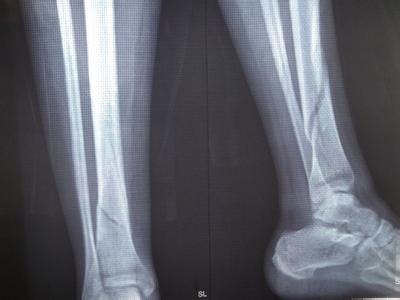

核心提示:骨折一般指的是骨的完整性和连续性中断。多数骨折由外伤引起,称为外伤性骨折或者创伤性骨折;少数可能由于骨骼疾病所致,如骨髓炎、骨肿瘤所致骨折破坏,受轻微外力即发生骨折,称为病理性骨折。很多人都想知道骨折后怎么样才能快速恢复,那么现在我来告诉大家吧。